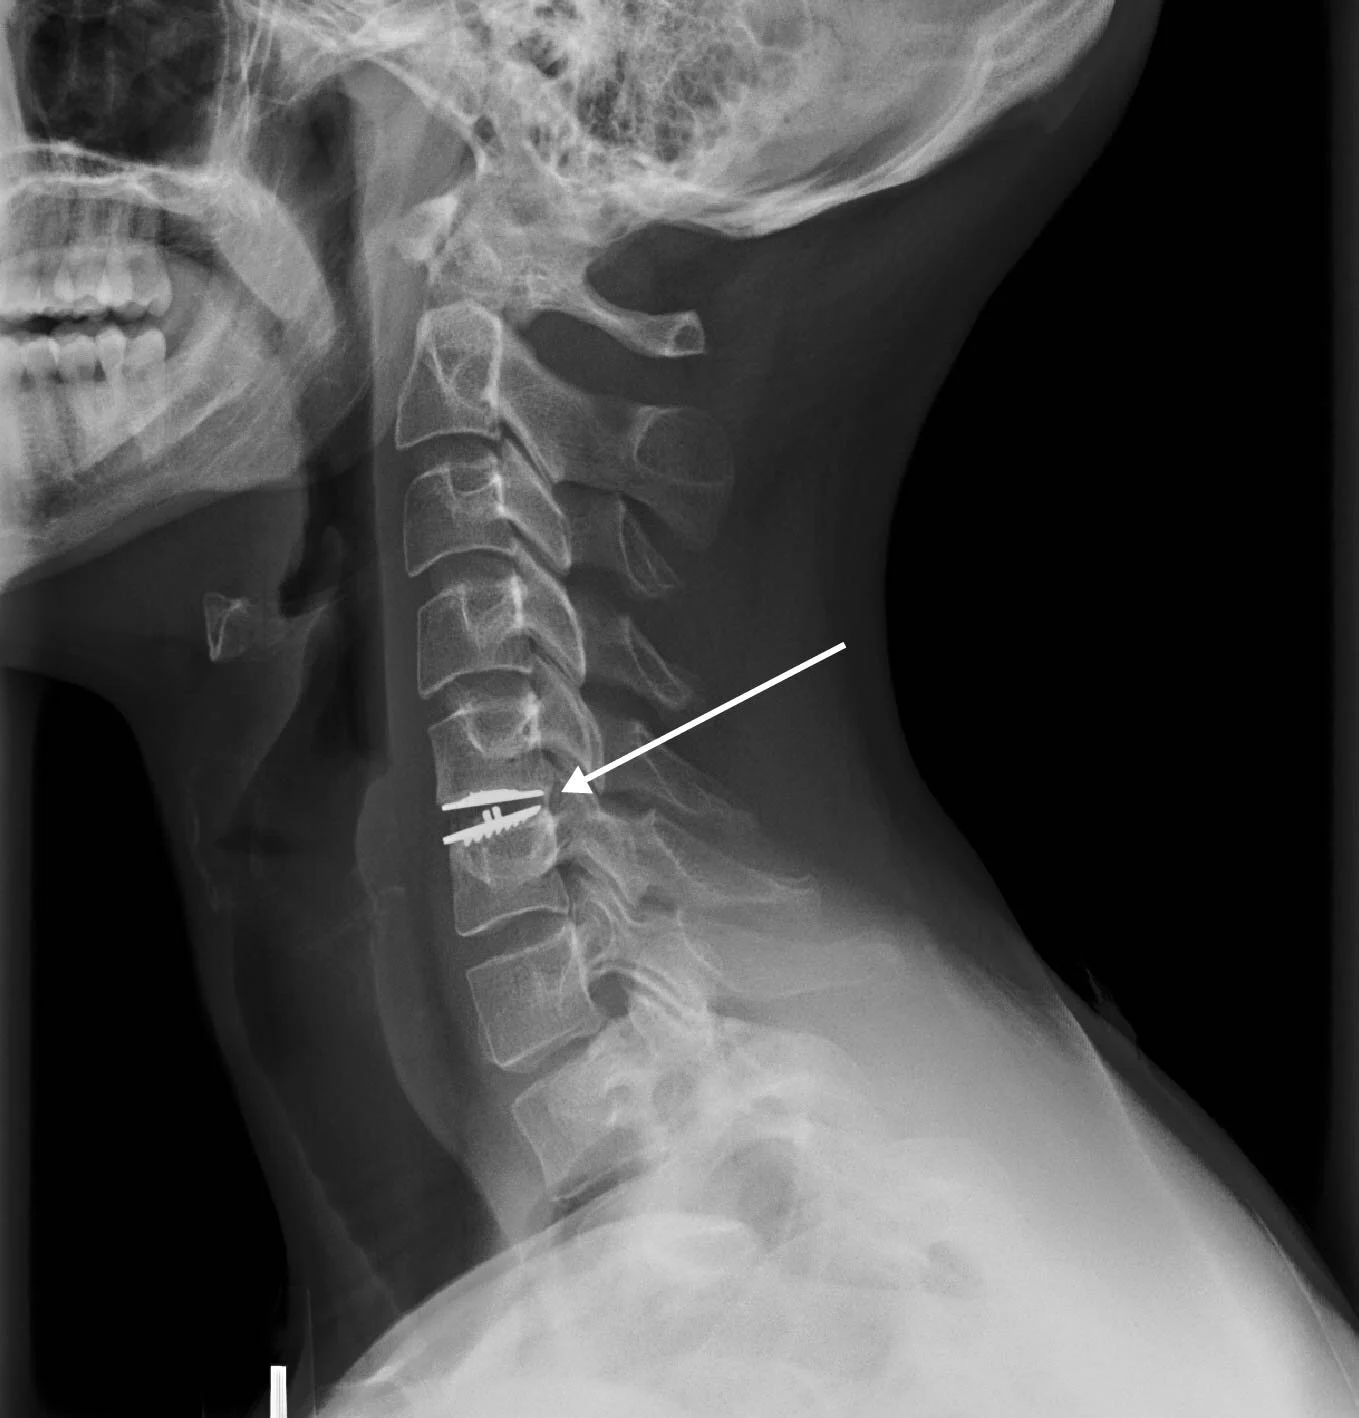

My 2015-2016 seasons of climbing were thwarted by a combination of PhD qualifying examinations and a severely herniated disc between C5-C6 vertebrae which paralyzed my right arm. In addition to being unable to lift even a Nalgene with my right arm, my thumb and forefingers were numb. There was also a pain from the back of my head all the way to my right hand that I can only describe as electric fire which would pulse frequently and prevent me from sleeping. The recovery has been harrowing and slow, but I am back at it and cranking hard again pushing my limits. I learned a lot from chronic pain and the process of restrengthening perhaps worth reading about if you have a minute.

In an artificial disc replacement surgery at C5-C6, the doctor makes an incision in the front of your neck skin. The surgeon then pulls your neck muscles to the side and moves your esophagus out of the way to get access the ventral aspect of your spine. Once the spine is exposed, a mechanism that acts like a carjack holds the two vertebrae apart from one another while he cuts the disc from the bone and vacuums it away being careful not to damage the spinal cord. Using a bone saw, he then cuts grooves or drills guide holes into the vertebra in order to anchor the replacement disc. Using a hammer, he then pounds the metal replacement disc into place and verifies the position by x-ray. He then sews up the incision site you up and leaves you in a bed in a groggy state to recover. The whole procedure takes about 2-3hrs, pretty similar to my qualifying exam in that way. The qualifying exam was only the start of the massive undertaking of the PhD and the surgery was only the beginning of a long road of work to recovering the use of my arm.